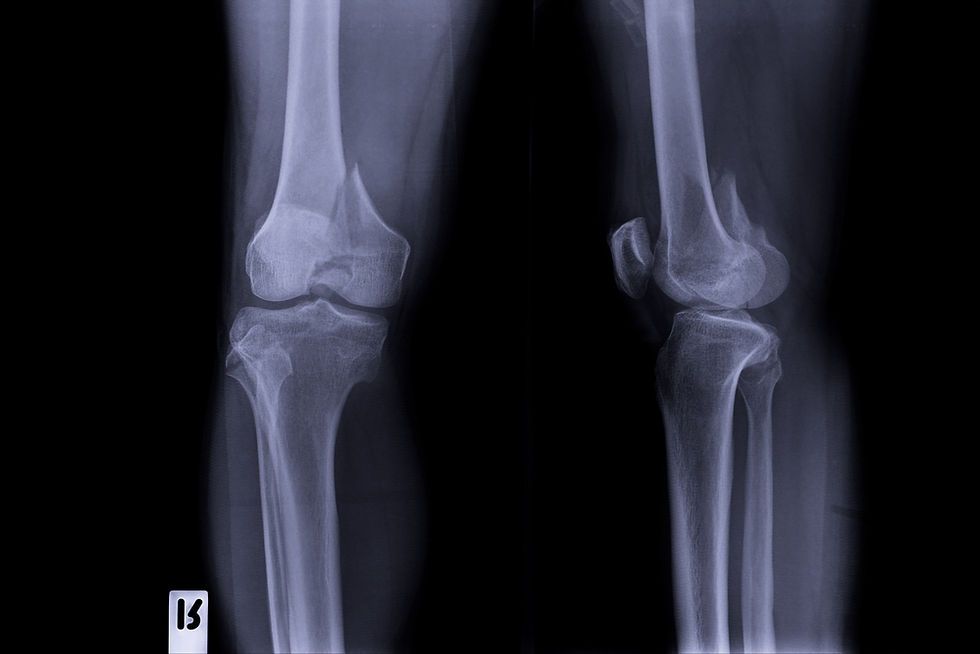

왼쪽 무릎과 고관절이 좋지 않다. 예전에 치료를 받으며 엑스레이 사진을 가지고 의사랑 이야기를 나눈 적이 있다. 의사가 내 왼쪽 무릎 사진을 보고 운동하는 사람이냐 물어보길래, 달리기랑 웨이트 한다고 했더니 한숨을 푹 쉬었다. 걸어 다닐 때 아프지 않은지 물어보았다.

의사에게, 10km 20km 뛰어다닌다고 그랬더니 어이를 상실하는 표정이었다. 어떻게 그게 가능하냐며. 의사 말로는, 이미 연골은 거의 다 없어진 상태고 뼈가 갈려서 석회가루가 쌓여있다고 한다. 어떻게 그렇게 되는지는 모르겠지만, 석회가 많이 생겨서 오히려 그게 열이 받으면 연골처럼 작동을 하는 게 아닌가 싶더란다.